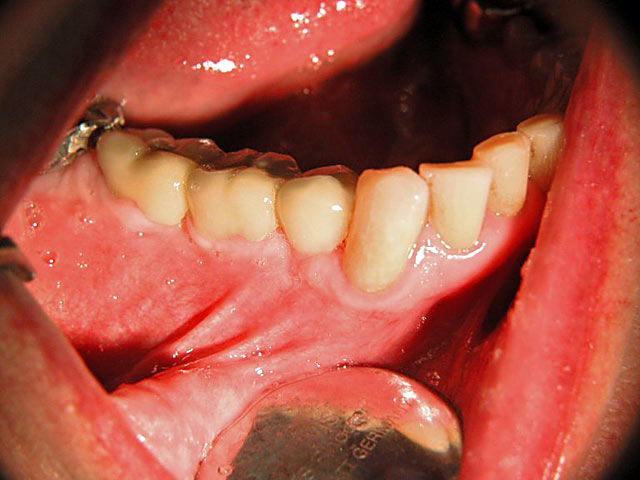

Die folgenden Patientenfälle sollen Ihnen einen Einblick in die Möglichkeiten der modernen Implantation geben.

Frontzahn-Implantation: